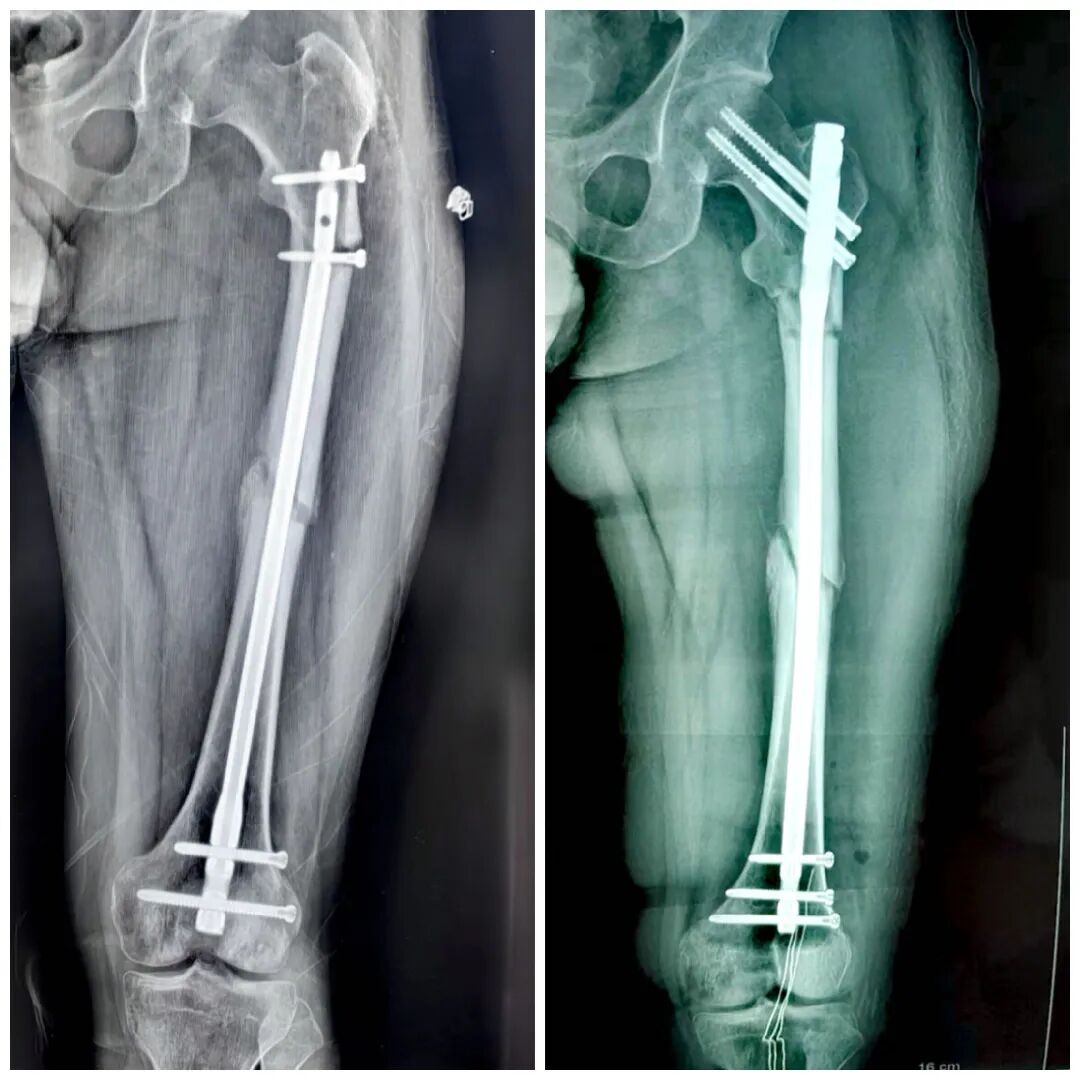

取出内固定,恢复自由身

逆行髓内钉:距膝关节间隙20 cm以内的骨干骨折、股骨髁上及髁间骨折。